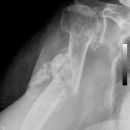

Subcapitale Fraktur und Tuberculum majus